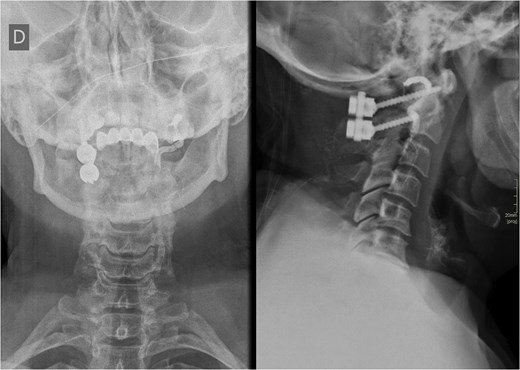

Before transferring the patient to the interventional radiology suite, a salvage contralateral unilateral C1-C2 fixation with C1 laminectomy and posterolateral fusion was performed, achieving full spinal cord and dura decompression. CT angiography revealed complete left VA occlusion at the C1 groove, likely from thrombosis, with the right VA patent and dominant. To prevent rebleeding during revascularization, the injured VA was occluded using coils and liquid embolic agents (Fig. 2).

Postoperative X-ray of the cervical spine showing contralateral unilateral C1-C2 fixation and the left VA opacified with a radiopaque contrast agent.